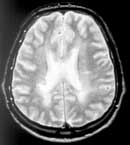

Данные МРТ головного и спинного мозга позволили выявить очаги снижения интенсивности сигнала (чаще перивентрикулярные, реже одиночные в ножках мозга, полушариях) в Т-1W режиме и одновременного повышения интенсивности сигнала в Т-2W режиме в начальном периоде РС у 53 (70,7%) в головном и у 41 (54,7%) - в спинном мозге. Несмотря на наличие четких клинических симптомов РС диагностическая значимость МРТ головного и спинного мозга в начальном периоде РС не высокая (Рис. 1, 2).

Рис 2. Расширение желудочковой системы.